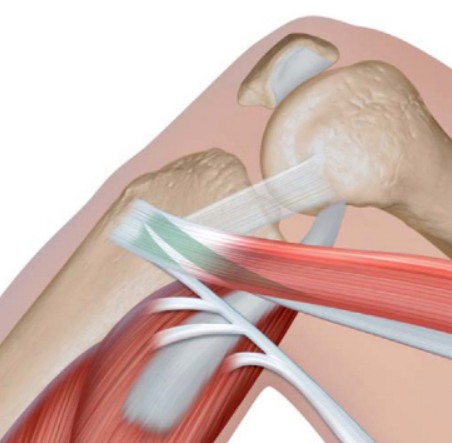

跟腓韧带是踝关节外侧韧带复合体核心组成,起自外踝尖、止于跟骨外侧,主要限制踝关节内翻、维持外侧稳定。当出现撕裂、断裂或慢性松弛,导致踝关节反复扭伤、不稳且保守治疗3个月无效时,需行跟腓韧带重建术,采用免打结锚钉缝合固定,操作简便、固定可靠。

固定原理:利用免打结锚钉的自锁定功能,将移植物两端分别与外踝、跟骨骨面固定,通过缝线张力维持移植物稳定,替代传统界面螺钉或多枚普通锚钉,无需复杂操作。

4.外踝端锚钉固定

于外踝尖原韧带起点新鲜化骨面,垂直骨面植入1枚免打结锚钉;将锚钉配套缝线穿过肌腱一端(距末端1-2cm处,穿1-2次),牵拉肌腱调整至中等生理张力,拉紧缝线触发锚钉免打结自锁定,使肌腱端牢固贴合外踝骨面。

5.跟骨端锚钉固定

将肌腱自然牵拉至跟骨外侧原韧带止点新鲜化骨面,确保肌腱无扭转、贴合原韧带走行;于该骨面垂直植入第2枚免打结锚钉,配套缝线穿过肌腱另一端(同法,距末端1-2cm处),微调肌腱张力(踝关节中立位自然绷紧),拉紧缝线完成免打结锁定。